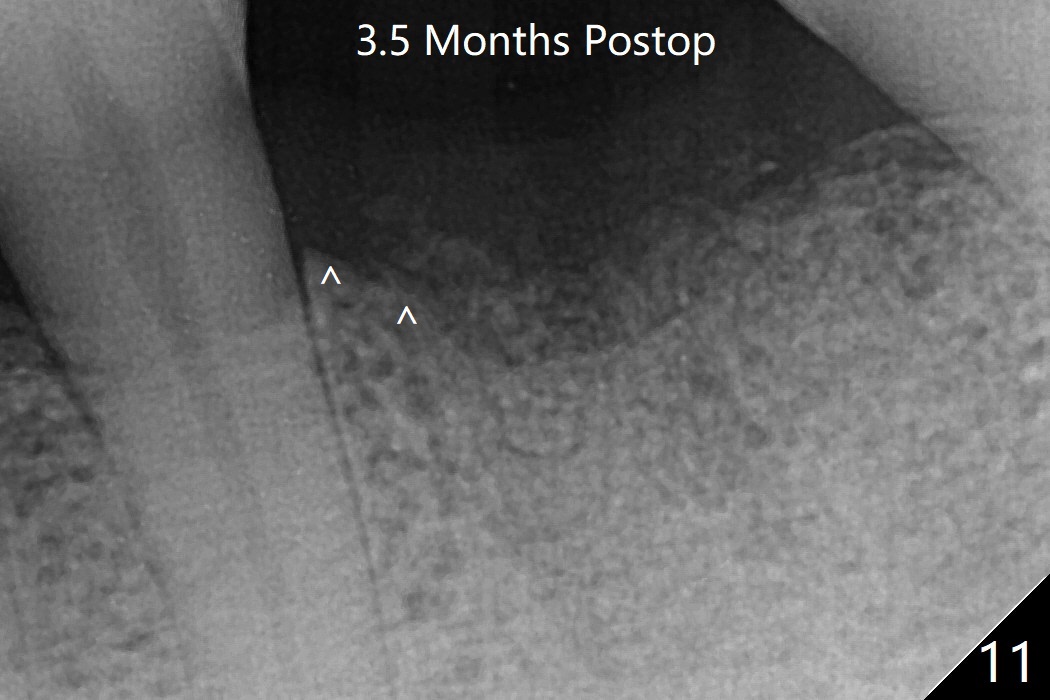

In spite of no apparent loss of bone graft (Fig.4,10), the graft seems to shrink in height 3.5 months postop (Fig.11), while the crest decreases (compare Fig.1 and 11).53岁男左下6因近中根周围阴影(图一)拔除植骨(图四)。术后16天骨粉好像没有失去(图十),但是术后3.5月骨粉仿佛收缩(图十一),牙槽嵴接近牙槽窝处下降(比较所有图)。